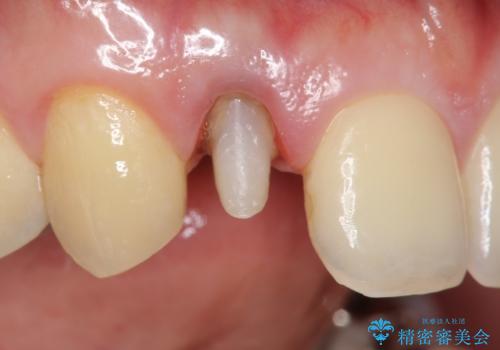

- 金属を使っていない被せ物に替えたいといらっしゃった方の症例です。

再根管治療終了後、オールセラミッククラウンによる補綴を行いました。

- オールセラミッククラウン(スペシャル)…¥130,000、仮歯…¥10,000、ファイバーコア…¥20,000、精密根管治療費別途費用は治療当時の料金となります